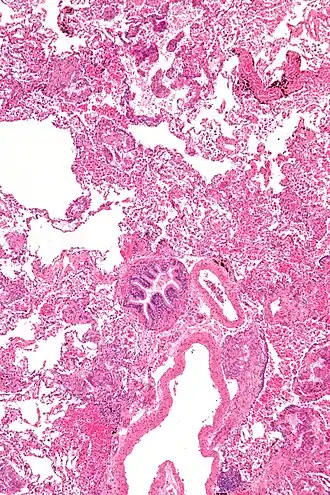

| Micrografia de uma linfangioleiomiomatose. H&E stain. | |

A linfangioleimiomatose (LAM) é uma rara doença intersticial pulmonar idiopática que afeta exclusivamente mulheres, tipicamente durante seus anos reprodutivos, caracterizada pela proliferação anormal de células de músculo liso nos pulmões e nos linfáticos retroperitoneais e torácicos. [1]